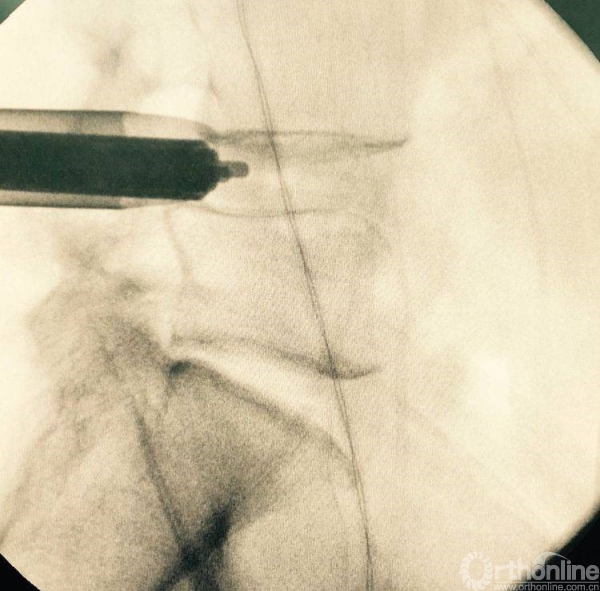

植入椎板钉、开路椎、扩展管、克氏针以及动力钻等应用

植入经皮椎弓根钉并加压

术后正、侧位片

植入钉棒位置较为合理

矢状位融合器、植骨位置及滑脱复位情况